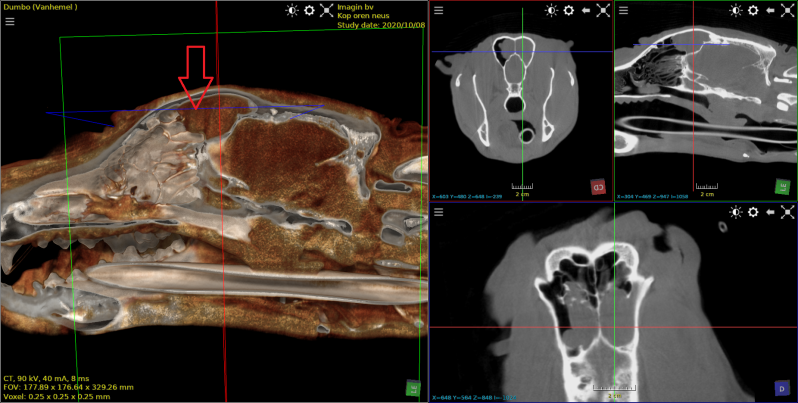

Hond met chronische oorontsteking.  Aantasting binnen en middenoor. Bulla tympanica gevuld met massa of vocht. Aantasting van de frontale sinussen . Osteolyse en nieuwbeen vorming.

kat met voorgeschiedenis van poliepen in buis van Eustachius, middenoor en oorgang.

Geopereerd in januari en hervallen in mei. Duidelijke aantasting van bulla tympanica en etter subbutaan en in het middenoor.